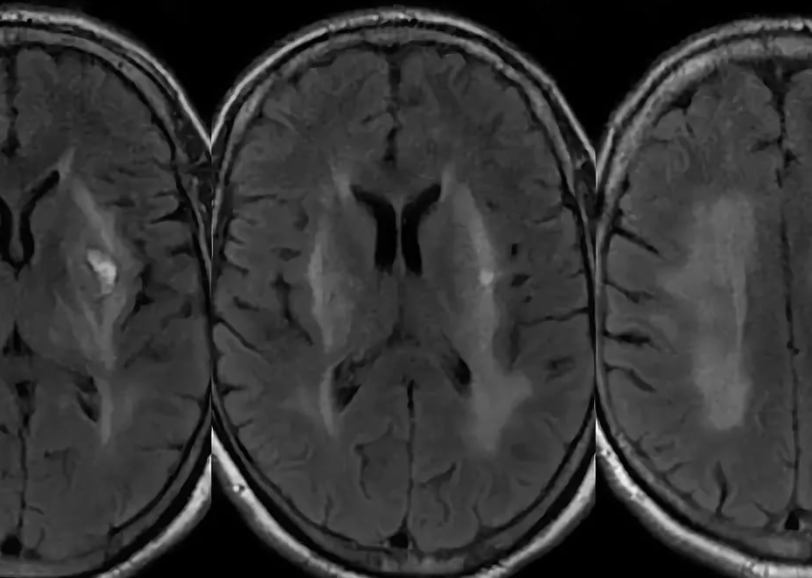

Энцефалопатия

Сотни тысяч нейронных связей должны перегруппироваться и встроить в общую систему новые клетки памяти, образованные в течении дня. Бывает наоборот, необходимо отсоединить уже неработающие связи с повреждёнными или сгоревшими нейронами от физического напряжения и стресса, неважно какого рода.